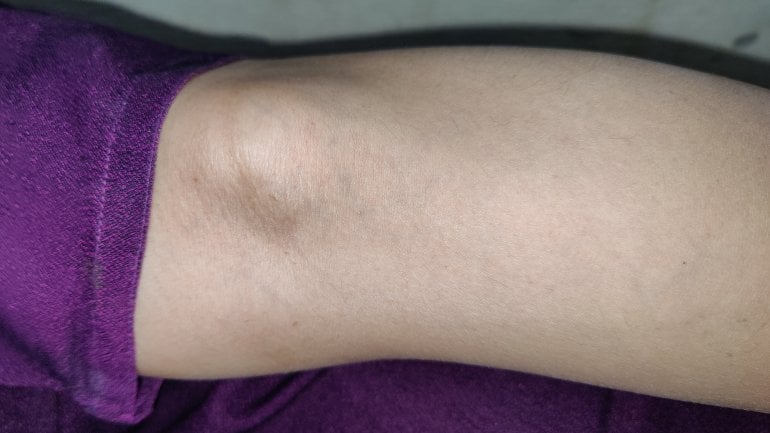

Schmerzen in der Kniekehle: Was kann es sein?